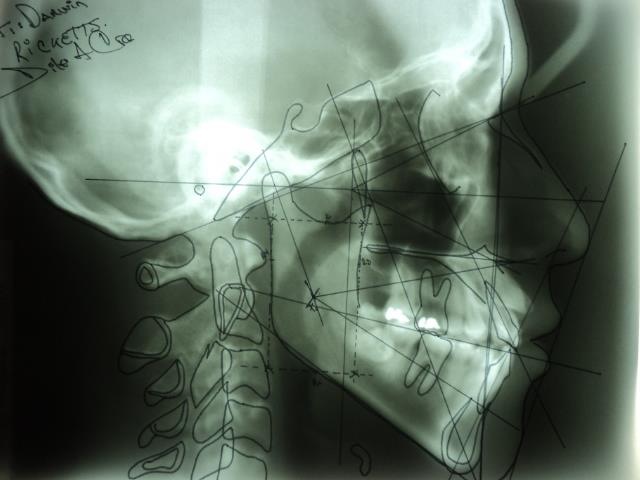

ESTUDIOS CON RADIOGRAFIAS DOCTOR DILER CRUZ

LAS RADIOGRAFIAS SON DE VITAL IMPORTANCIA PARA LOS TRATAMIENTOS EN

ORTODONCIA; BUENOS DIAS LES SALUDA LA CLINICA DE ORTODONCIA Y

ORTOPEDIA MAXILO FACAIAL